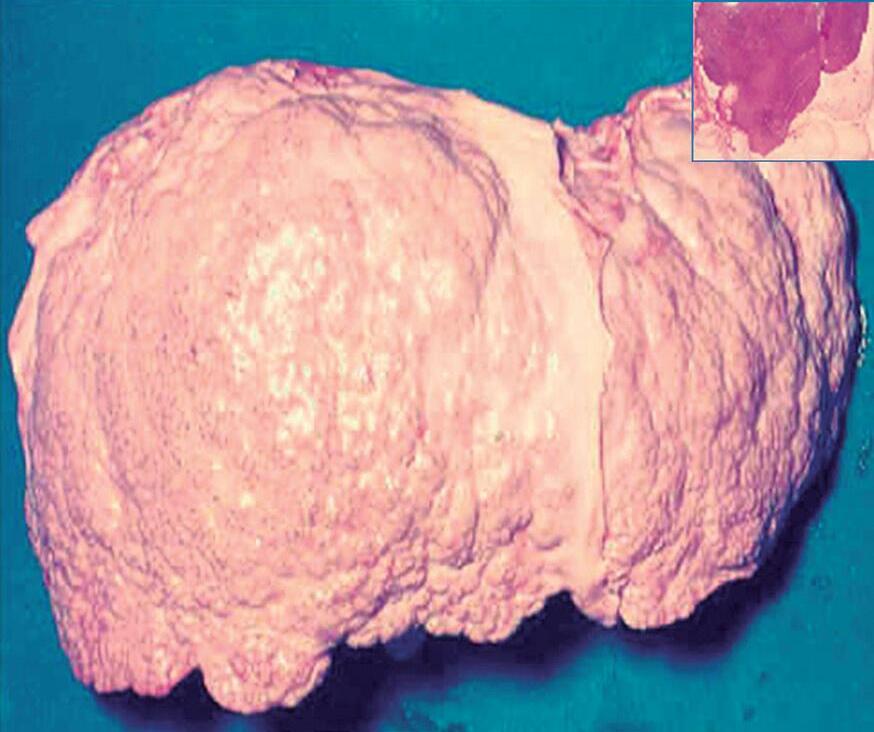

Fig. 15-8. (a) ultrassonografia (usG) de fígado cirrótico. (b,c) Correlação com a anatomia e a histologia.